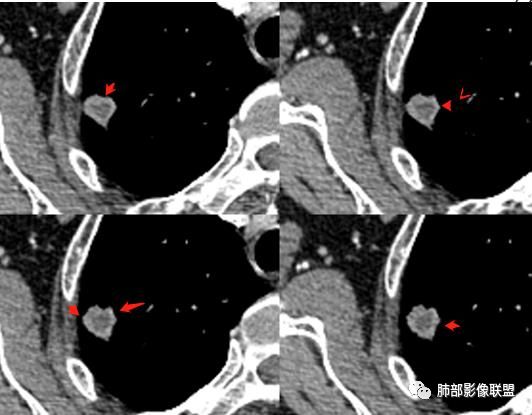

4.增强扫描成明显环形强化,中央液化坏死,内壁清楚且较为规整。

1.肺鳞癌是容易坏死,但如此小的结节出现影像明显可见的坏死区,且内壁如此清楚规整,我们临床实践中肿瘤非常少见,重要的事情说三遍!!!

好发于肺尖或尖后段胸膜下的密度不均的结节什么病最常见?结核!

小病灶常常出现空洞的什么病最常见?结核!

空洞内外壁都很清楚的什么病最常见?结核!

周围伴随小结节及条索影的什么病最常见?结核!

老年男性痰中带血为主诉常见的还是肿瘤及结核。